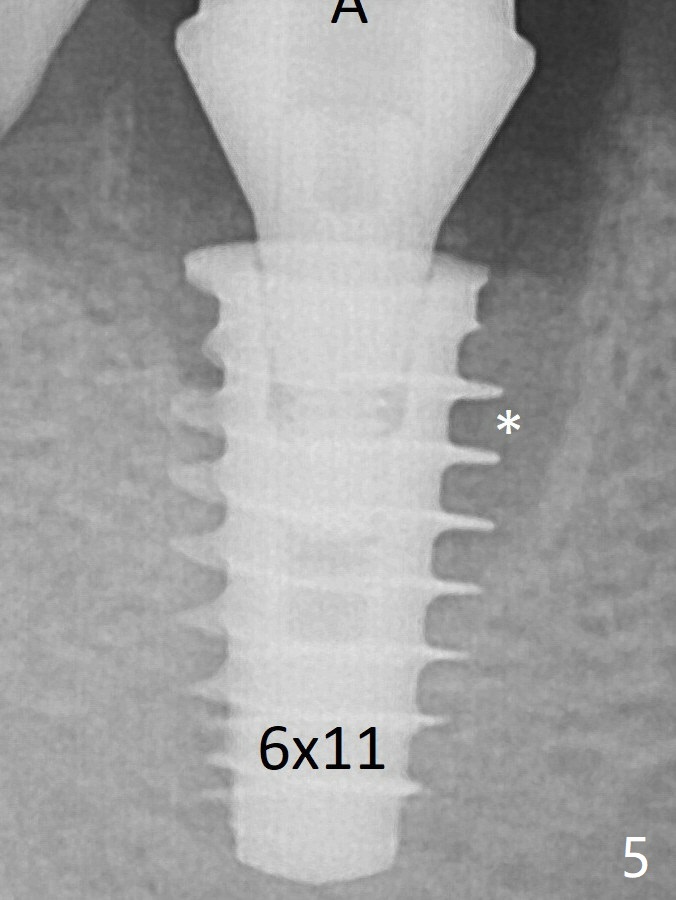

To reduce socket gap (*), a 6 mm IBS implant is inserted with >50 Ncm (Fig.5).  What is unexpected is heavy reduction in the height of a 6.5x4(3) mm abutment (A) because of the short crown height of the lower posterior teeth (Fig.1) and supraeruption of the tooth #3.  The immediate provisional is unstable postop.  The remade one dislodges soon, so does the abutment (Fig.6, 3 months postop).  It appears that bone pattern in the distal socket changes.